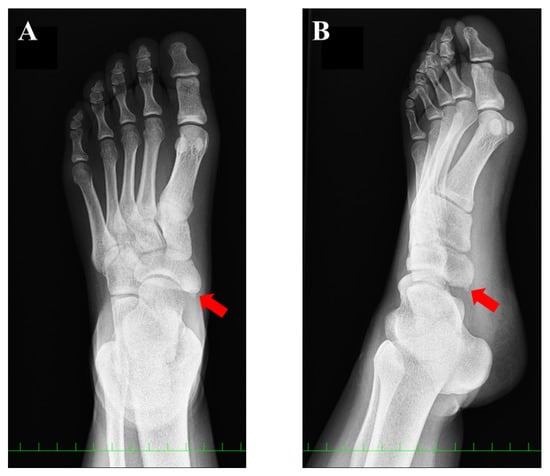

2. Case Presentation